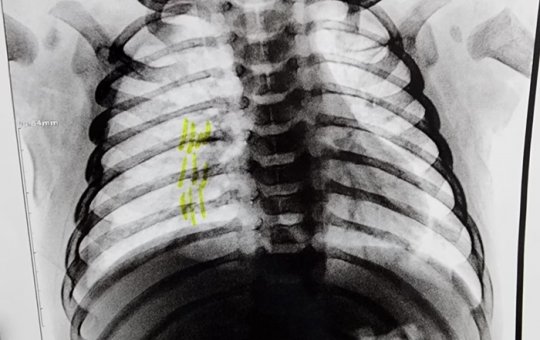

Padrasto é preso suspeito de quebrar costelas de bebê de 2 meses

Prisão ocorreu após o Conselho Tutelar da cidade acionar as autoridades